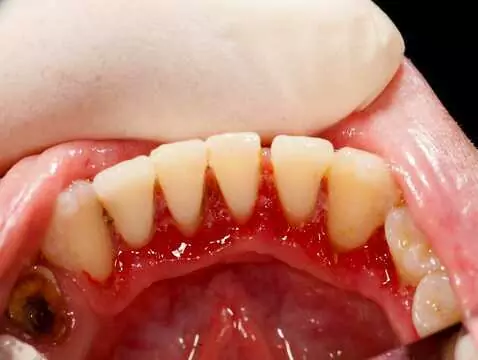

La gingivite est associée à une infection bactérienne. Si l'inflammation elle-même n'est pas contagieuse, la bactérie responsable de son développement peut se transmettre d'une personne à l'autre,...

Le tartre inesthétique peut apparaître sur les dents de tout un chacun. Est-il nocif ? Faut-il l'enlever ? Combien cela coûte-t-il ? Nous avons rassemblé les conseils en un seul endroit.

Un sourire beau et sain est le rêve de beaucoup d'entre nous. Une bonne hygiène est la première étape pour obtenir le sourire de vos rêves. Les services de détartrage et de sablage sont disponibles...